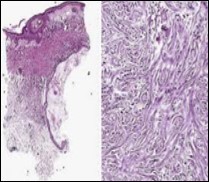

Figure 3.Desmoplastic trichoepithelioma exhibiting accumulated basaloid epithelial cells disseminated amongst a background of abundant fibrous tissue stroma and an attenuated superimposed epidermis 10.

Figure 4.Desmoplastic trichoepithelioma depicting cords and aggregates of basaloid epithelial cells with encompassing dense, compact fibrous tissue stroma 11.

Figure 5.Desmoplastic trichoepithelioma enunciating several horn cysts, nests of basaloid cells, an enveloping desmoplastic stroma and thinned out superimposed epithelium 12.

Figure 6.Desmoplastic trichoepithelioma displaying few horn cysts, nests of basaloid cells and an abundance of desmoplastic, fibrotic stroma with an attenuated squamous epithelial lining 13.

On gross examination, frequently the tumours are gradually progressive, grey/white or flesh coloured, indurated, non ulcerated with a central depression and a magnitude varying within a few millimetres. The well circumscribed lesion is symmetrical, confined to papillary dermis and upper two thirds of reticular dermis. Emergence of narrow strands of basaloid epithelial cells, numerous horn cysts, a dense, encompassing fibrous tissue stroma, foreign body granulomatous reaction, several foci of calcification and articulation of osteoma within the lesion provide diagnostic characteristics 3, 4.

Nests, strands and miniature cords of basaloid epithelial cells of variable dimension, encompassed within a dense fibrotic tissue stroma are observed within the upper and mid-dermis. Cellular aggregates are rimmed with collagen bundles, multiple horn cysts appear within the stroma and a layering of stratified squamous epithelium is enunciated. Foci of calcification are apparent. Mitotic figures, peripheral palisading, apoptotic bodies aggregated within the epithelium or cellular and nuclear pleomorphism are absent 3, 4

Commonly, miniature strands of basaloid cells are encompassed within a desmoplastic stroma in association with keratinous cysts, usually abutting or attached to basaloid cell aggregates. Superimposed epidermis demonstrates a mild atrophy in accompaniment with enlarged cords of tumour cells aggregated within the mid - dermis. Connective tissue hyperplasia is observed within the horn cysts 4, 5.

Lesions are generally superficial and infrequently invade lower dermis. Tendency for peri-neural or intra-neural infiltration, cogitated in adjunctive cutaneous carcinomas, is exceptional in desmoplastic trichoepithelioma. Nevertheless, desmoplastic trichoepithelioma can be exemplified as a component of particularly desmoplastic, cutaneous carcinomas demonstrating foci of peri-neural involvement 4, 5. Figure 1, Figure 2, Figure 3, Figure 4, Figure 5, Figure 6, Figure 7, Figure 8.